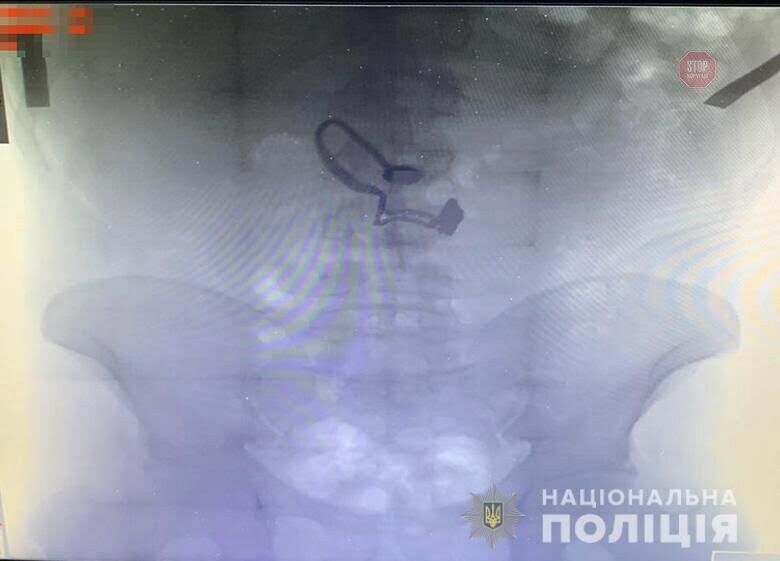

У чоловіка був знайдений гаманець потерпілої. Згодом він зізнався правоохоронцям, що зірваний ланцюжок проковтнув. Під час медогляду на рентген знімку затриманого лікарі виявили прикрасу.